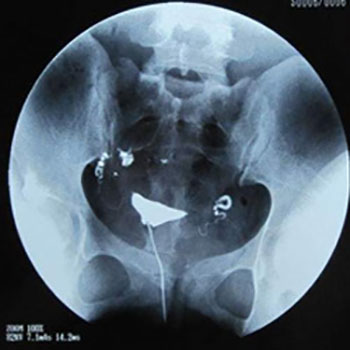

不孕必查项:输卵管造影检查对比其它造影

在造影检查上,咱们医院所采用的是ICM超高清无痛输卵管造影,它是与湘雅、省妇幼等三甲医院同步的检查技术,采用进口造影剂,对身体没有影响。高清显影能看到输卵管内部和宫腔、盆腔情况,达到公立三甲品质。